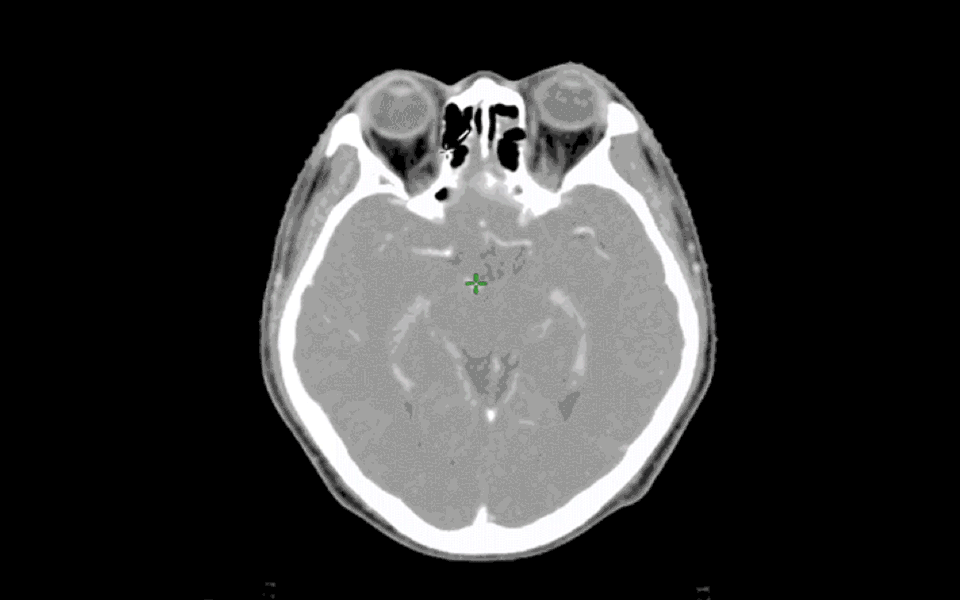

智能化利用大数据、机器学习,实现智能器官勾画,提高放疗工作人员的工作效率与工作质量,降低出错概率

智能勾靶无缝连接AiContour和AiPlan系统